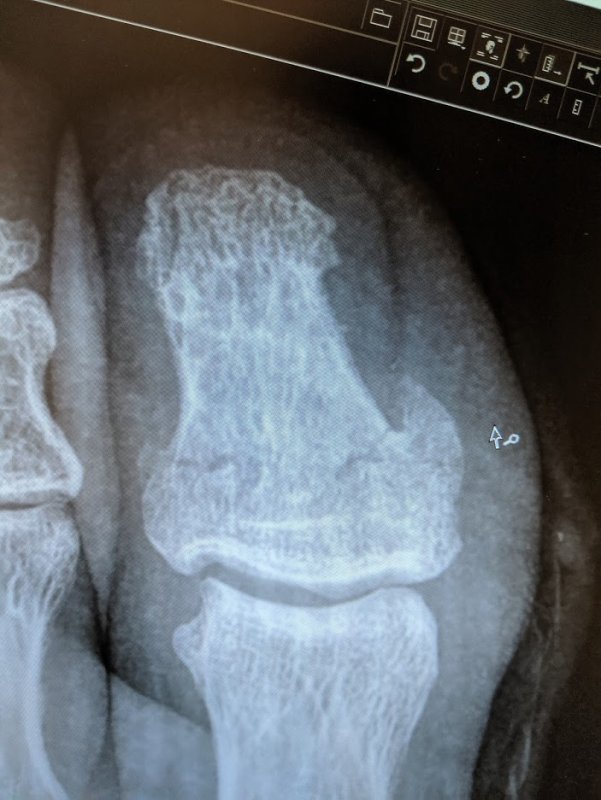

So there i was, flying down the mountain at a blinding warp speed, skillfully dodging the murder-boulders, covid-walkers and tick-rappellers clearly on my way to the supreme galactic emperor of KOM's. But the mountain had other ideas... As a I crested the climb that even the most burly of hike-a-bikers would reel in terror at, i jumped up on the pedals and hit the throttle down the tight corridor straightaway of overgrown shrubbery constricting down on me like a giant green Boa. Tucking down deeper, the leaves become a verdant starfield whizzing by, i could see the exit closing down on me but i knew i could make it if it hit the afterburners. It was here the mountain mounted its final assault on me. It dug deep into its cache of finest hook roots and sent it rocketing up the earths crust hoping it would find its way on a collision course with my two-wheeled Carbonium rocketship. Blindsiding me, that dirty hookroot just barely managed to find my biggest weakness--my size 14 clodhoppers. In the nick of time, it stretched that root as far as it would go and managed to barely connect with the tip of my shoe as it apexed on the massive power downstroke. Grabbing with all of its worldly might, it wrestled my foot free from the pedal, wrapped itself around my grand large toe and stood fast trying to anchor me to terra firma while my mighty steed continued its forward trajectory. As i was separated from my vehicle, i was fortunate to land in the soft, pillowy raspberry thicket nearby to collect my thoughts, wits and ponder the unknown whereabouts of my ride. Gazing down upon my foot, although the root had broken free, however, its grip upon me wasn't the only thing seemingly broken. It appears my grand toe had decided it would need to sacrifice itself to prevent a more catastrophic disaster--a noble action indeed! So, broken and beaten, i collected my vehicle from the mob of angry greenbriar, set out to return to base and survey the damage. The diagnostic bot said the bike is fine but the toe is done. You're on sick leave for at least a month dude.